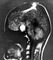

Основными методами диагностики аденомы гипофиза являются клинико-биохимическое и рентгенологическое исследование (краниография), радиоиммунологический метод, компьютерная томография, ЯМР-томография. При подозрении на А. г. в первую очередь производят рентгенокраниографию (рис. 1) в двух проекциях и томографию области турецкого седла для выявления характерных признаков внутриселлярного объемного процесса, вызывающего изменения костных структур — остеопороз, деструкцию спинки турецкого седла и др. Характерной является двухконтурность дна турецкого седла. Установить присутствие опухоли, особенности ее структуры (солидная, кистозная и др.), направление распространения и величину позволяет компьютерная томография (рис. 2) с контрастным усилением. ЯМР-томография при аденоме гипофиза позволяет в некоторых случаях выявить инфильтративный рост опухоли (рис. 3). При подозрении на латеральный рост опухоли (в сторону кавернозных синусов) проводят церебральную ангиографию. С помощью пневмоцистернографии обнаруживают смещение хиазмальных цистерн, а также признаки «пустого» турецкого седла (см. Гипофиз).